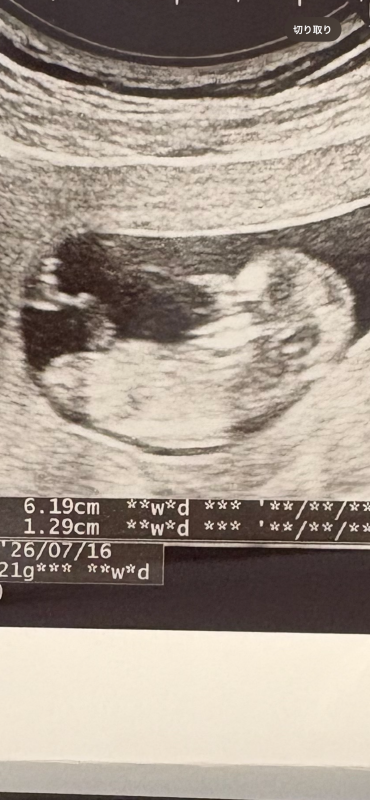

赤ちゃんのエコー写真について

赤ちゃんのエコー写真についてですね。

首の後ろに見える黒い部分はNTと言われる部分になると思います。

どの赤ちゃんにもみられます。

実際の暑さなどはこちらではわからないことになりますので、また次回の健診の際に先生へご確認いただけたらと思います。